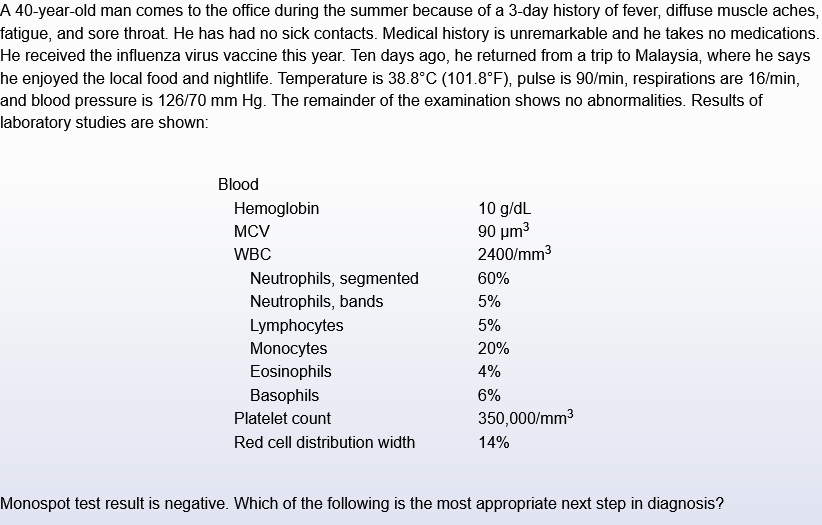

heterophile antibody test is used to dx…

EBV/mono

“monospot” test

do hiv pcr

mono-like sx & leukopenia? hiv until proven otherwise